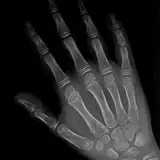

Over 2,100 interactive radiology cases, curated by radiologists for your level of training. Scroll, window, and view cases full screen — just like on PACS. Click linked findings in each writeup to jump straight to them on the image. Cases include sample reports, a focused discussion section, original illustrations, and videos.

PACSで期待されるツールを完備した完全インタラクティブな症例 — スクロール、ウィンドウ調整、ズーム、パン、計測、ROI、フルスクリーンモード。